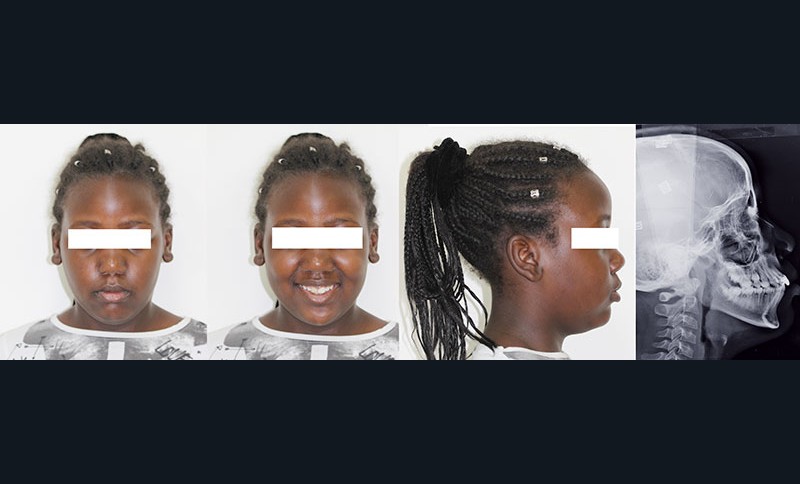

Situation clinique (fig. 1 à 9)

Orlhane B., 10 ans, est adressée à l’unité fonctionnelle d’orthodontie de l’hôpital Bretonneau par son dentiste suite à un traumatisme sur la 11. Le trait de fracture est infra-osseux et ne permet pas la réalisation d’une restauration prothétique de cette dent. Le praticien nous demande de réaliser une extrusion orthodontique afin d’égresser la dent sans que son parodonte suive le mouvement dentaire et d’augmenter ainsi l’espace biologique. La longueur radiculaire permet ce mouvement (rapport couronne/racine postextrusion inférieur à 1) et un traitement à l’hydroxyde de calcium est réalisé transitoirement durant le déplacement orthodontique. L’obturation finale sera réalisée une fois que les limites du trait de fracture seront supra gingivales et permettront la mise en place d’un champ opératoire étanche.

À l’examen clinique, Orlhane présente une classe I biproalvéolie aggravée par 11 fracturée et 25 enclavée et une classe II canine légère gauche. Cette malocclusion est associée à une classe II squelettique par promaxillie sur un schéma facial hyperdivergent. Il est décidé de ne pas traiter la biproalvéolie et la classe II squelettique modérées d’origine ethnique chez cette patiente.